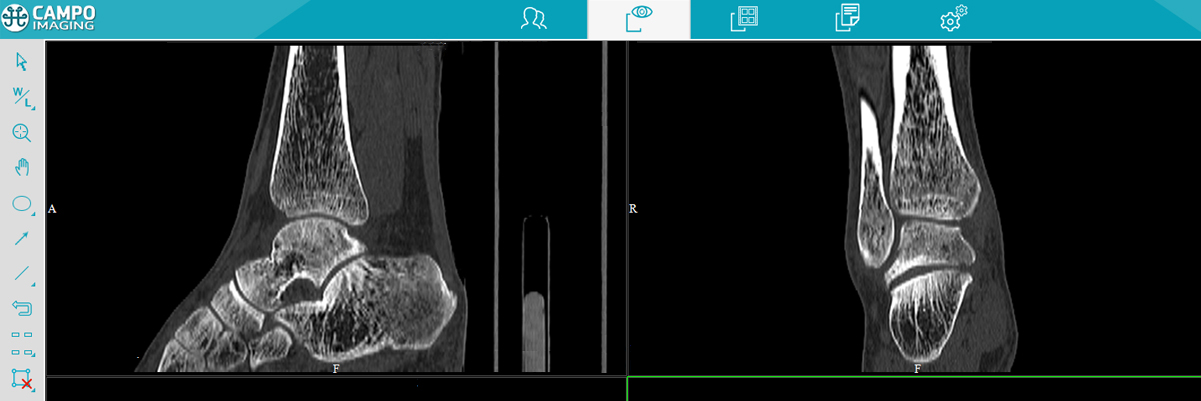

图像浏览

多平面重建

多平面重建